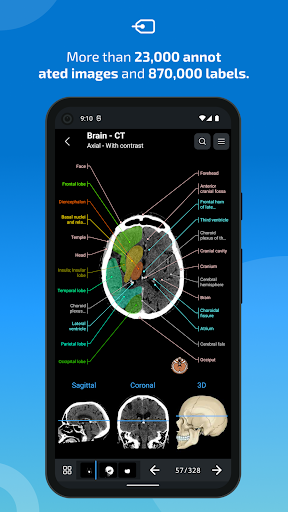

e-Anatomy memiliki lebih dari 26.000 gambar yang berisi serangkaian gambar dalam tampilan aksial, koronal, dan sagital serta radiografi, angiografi, gambar diseksi, bagan anatomi, dan ilustrasi. Semua gambar medis diberi label dengan cermat, lebih dari 967.000 label tersedia dalam 12 bahasa termasuk Terminologia Anatomica Latin.

- Ketuk label untuk menampilkan struktur anatomi

- Pilih label anatomi berdasarkan kategori